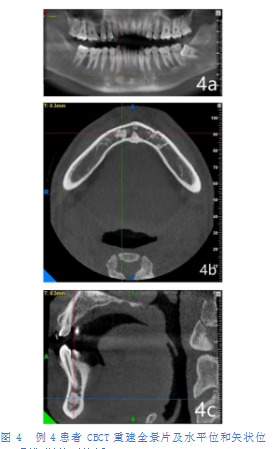

例4患者,男,32岁。CBCT重建全景片及水平位和矢状位显示:右下尖牙根尖下方可见一圆形磨玻璃状、均匀的团块高密度影,有许多骨刺呈放射状向四周发出,边缘呈毛刷状、羽毛状。影像显示其与周围牙齿牙根、颊舌侧骨皮质均未见明显粘连,周围骨质密度未见明显异常改变(中央硬化型,图4)。

\